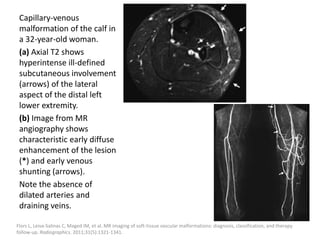

5-year-old with forearm VVM. (A) Coronal STIR shows predominant

hyperintense signal, lobulated contours, and dark signal intensity flow

voids due to phleboliths. (B) Coronal T1 shows iso- to mild hyperintense

signal within the malformation with some fatty atrophy of the underlying

muscle. (C,D) Axial pre-contrast and fat-suppressed post-contrast T1 show

gradual moderate enhancement within the VVM.

Masand P. Radiographic findings associated with vascular anomalies. Semin Plast Surg. 2014;28(2):69-78.